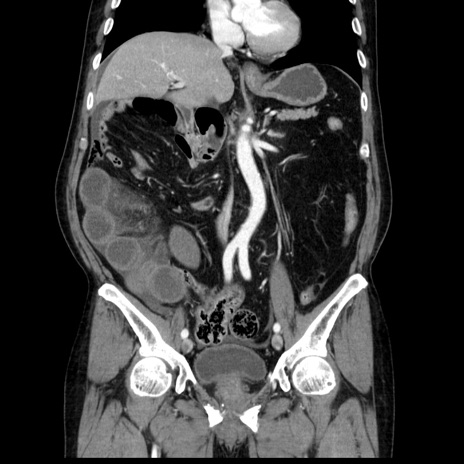

症例30(冠状断像)

【症例】80歳代男性

【現病歴】約6時間前から臍下部痛が出現。次第に腹部膨隆・背部痛も生じてきたため来院。背部痛の場所は変化しない。

【身体所見】意識清明、BT 36.3℃、BP  131/87mmHg、P 87bpm、SpO2 100%(RA)、臍周囲自発痛・圧痛あり、反跳痛なし、自発痛部位に一致して板状硬あり、腹部膨隆、腸雑音減弱、CVA tenderness両側陰性。